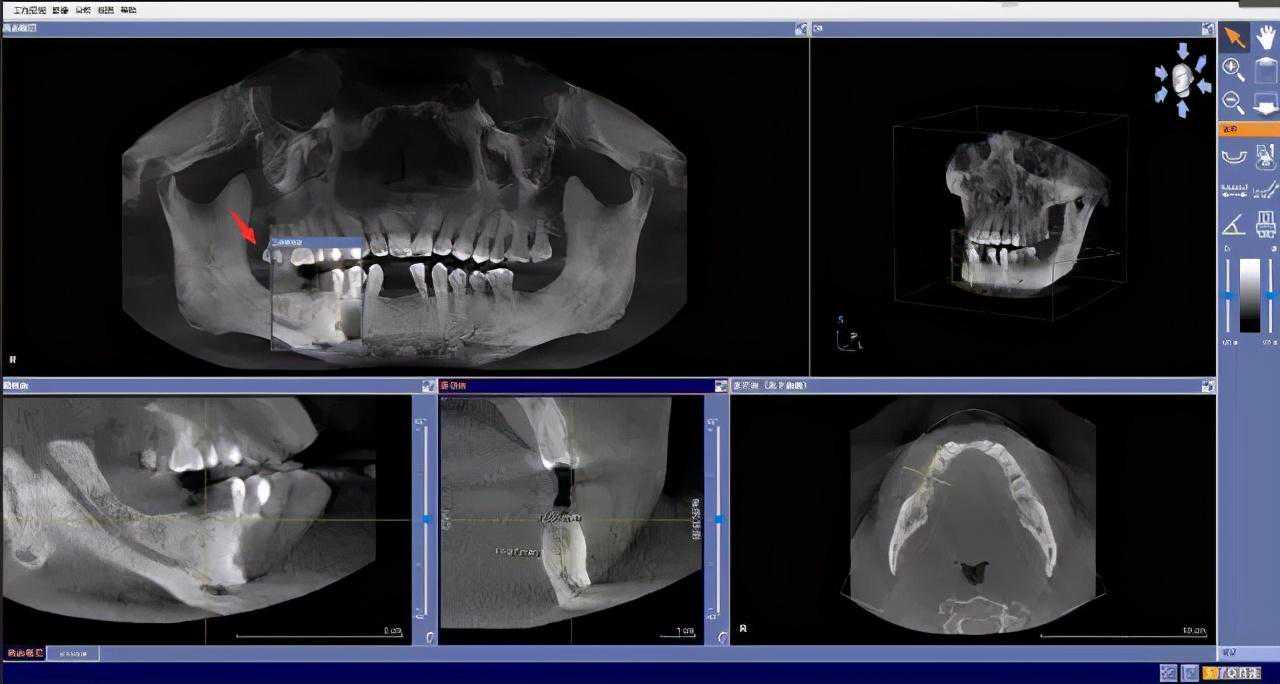

先要做一个口腔全景片、颌骨CT等

医生根据机器成像查看口腔的具体情况,

是否有炎症、牙槽骨的密度、吸收状况

以及邻牙组织、牙体组织等。

注明:此数据仅作模拟,不是确切种植数据。

如果仅靠双眼大致估测口内数据,是无法得到精准的高度、宽度的,也无法确认骨头吸收多少,是否需要植入骨粉。

对后期手术有一定的影响。

通过全景片可以“解剖”牙齿精确测量,适宜的种植角度也可确定,健康安全有保障。